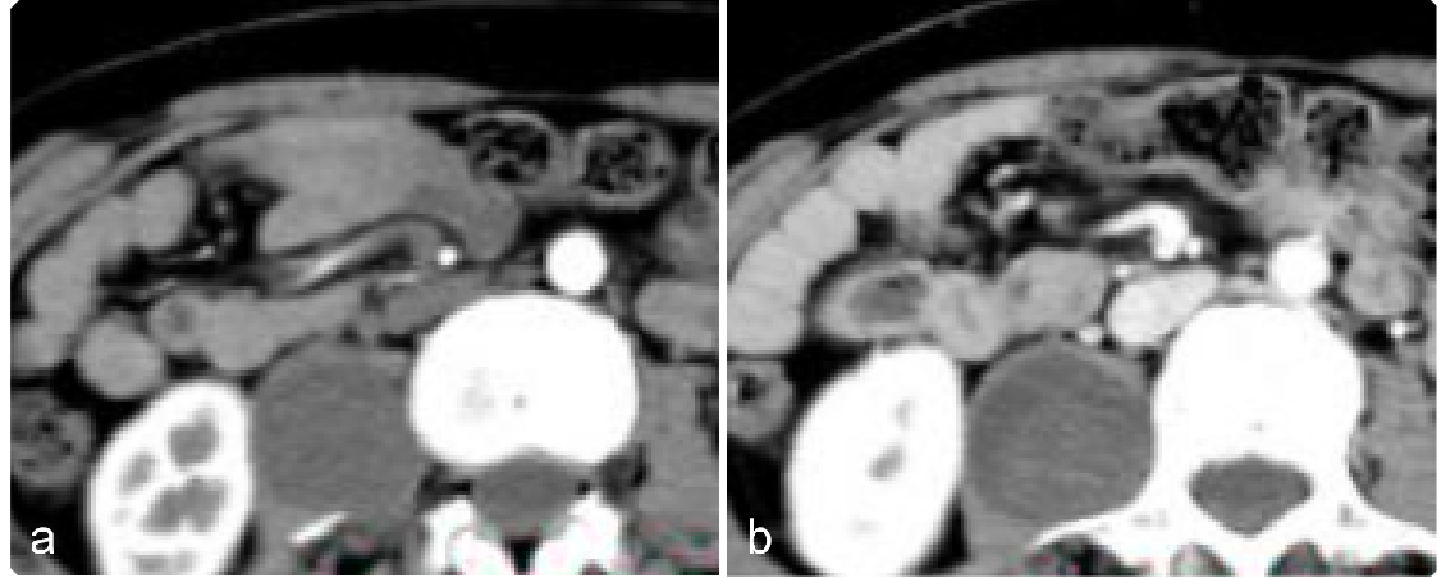

917bfe88330e9a51bacfc381b0a24818.png 病例 6:腹膜后平滑肌肉瘤2例

(① 血管内外;② 血管腔外)① 腹膜后肿块可见侵犯右肾血管、下腔静脉,密度不均匀,有囊变坏死,增强后边缘性延迟环状强化。② 腹膜后肿块与右肾血管,下腔静脉及腹主动脉分界不清,肿块密度不均匀,内可见囊变坏死区及高密度灶(平滑肌肉瘤瘤内如有出血,低密度区内可见高密度出血影,但通常不钙化),增强扫描呈明显不均匀强化,囊变区未见强化。